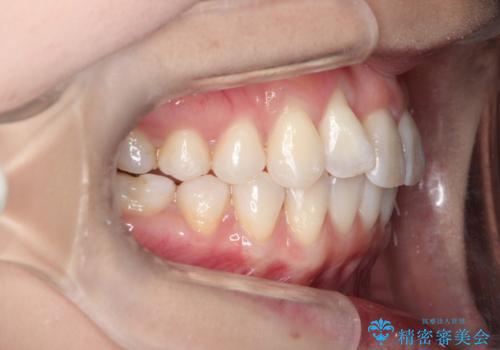

インビザラインによる矯正治療 前歯を整った歯並びへ

- 上の前歯のねじれを気にされて来院されました。

右上の前から2番目の歯が90度近くねじれて並んでいました。

こちらを当初セラミックでの治療をご希望でしたが、セラミック治療の限界と矯正治療のメリットをご説明をさせていただきました。

患者様に考えていただき、矯正治療で前歯をきれいにすることとしました。

インビザラインを使用して矯正することとしました。